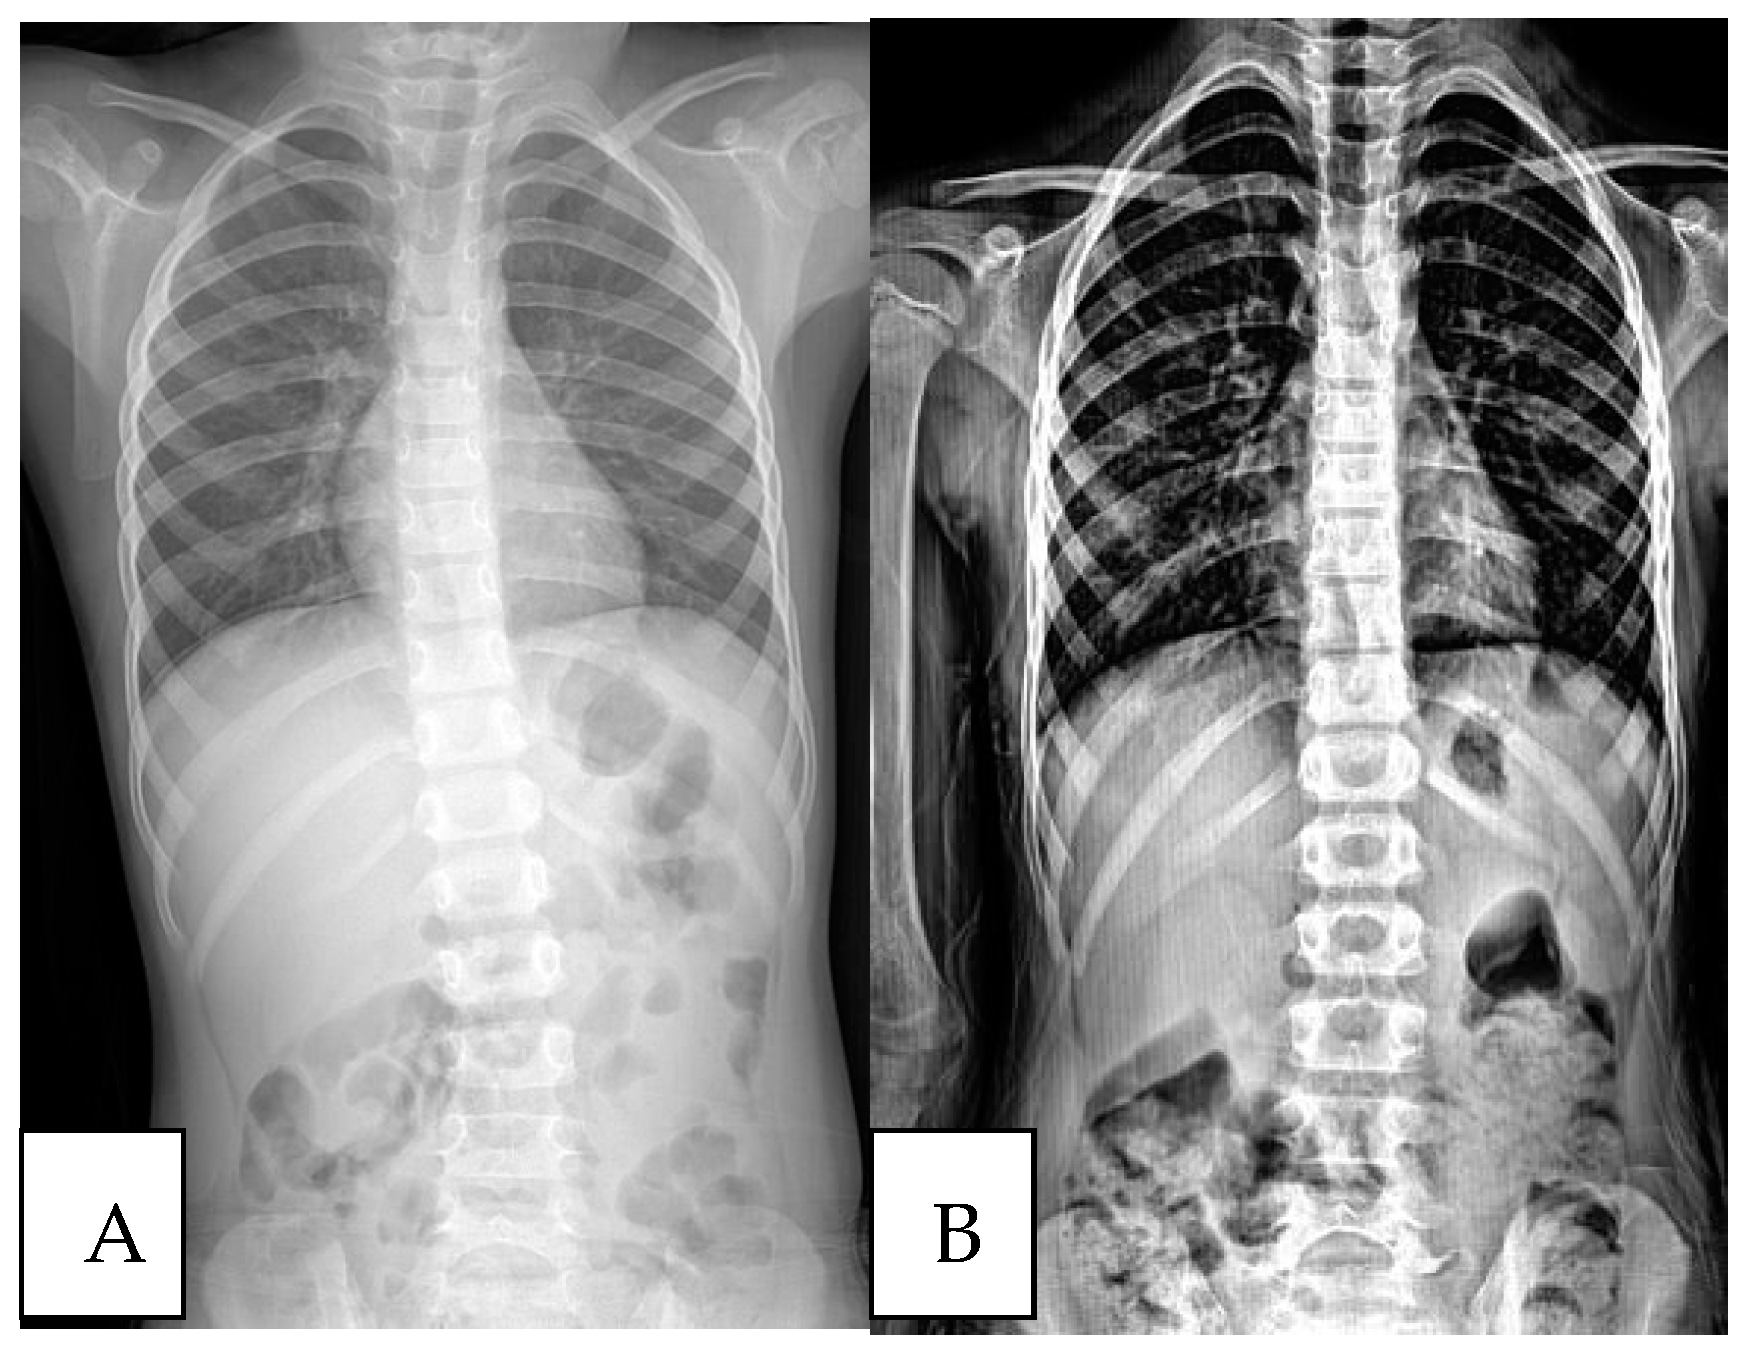

- Pan, X.-X.; Huang, C.-A.; Lin, J.-L.; Zhang, Z.-J.; Shi, Y.-F.; Chen, B.-D.; Zhang, H.-W.; Dai, Z.-Y.; Yu, X.-P.; Wang, X.-Y. Prevalence of the Thoracic Scoliosis in Children and Adolescents Candidates for Strabismus Surgery: Results from a 1935-Patient Cross-Sectional Study in China. Eur. Spine J. 2020, 29, 786–793. [Google Scholar] [CrossRef]

- Kockara, N.; Ucpunar, H. The Value of Standard Chest Radiography in the Diagnosis of Scoliosis. Ann. Med. Res. 2019, 26, 190–193. [Google Scholar] [CrossRef]

- Oh, C.H.; Kim, C.G.; Lee, M.S.; Yoon, S.H.; Park, H.-C.; Park, C.O. Usefulness of Chest Radiographs for Scoliosis Screening: A Comparison with Thoraco-Lumbar Standing Radiographs. Yonsei Med. J. 2012, 53, 1183. [Google Scholar] [CrossRef]